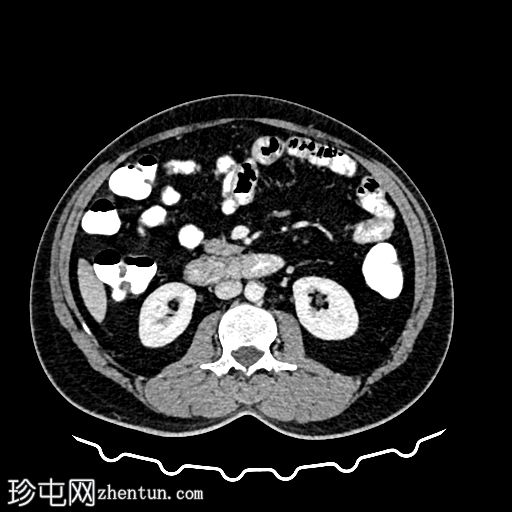

CT

轴位

平扫

轴位增强扫描

动脉期

门静脉期

冠状位增强扫描

乙状结肠旁可见两处小的脂肪衰减病灶。较小的病灶呈周边环状强化,伴有轻度邻近脂肪条索状改变 → 急性大网膜垂炎。

较大的病灶呈薄环状强化,周围无炎症 → 消退期/慢

性病

变。未见肠壁增厚,未见肠腔相通,无游离液体或积液。